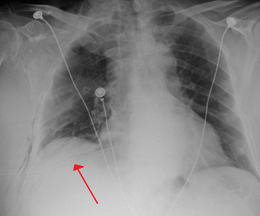

A large right-sided spontaneous pneumothorax (left in the image). An arrow indicates the edge of the collapsed lung